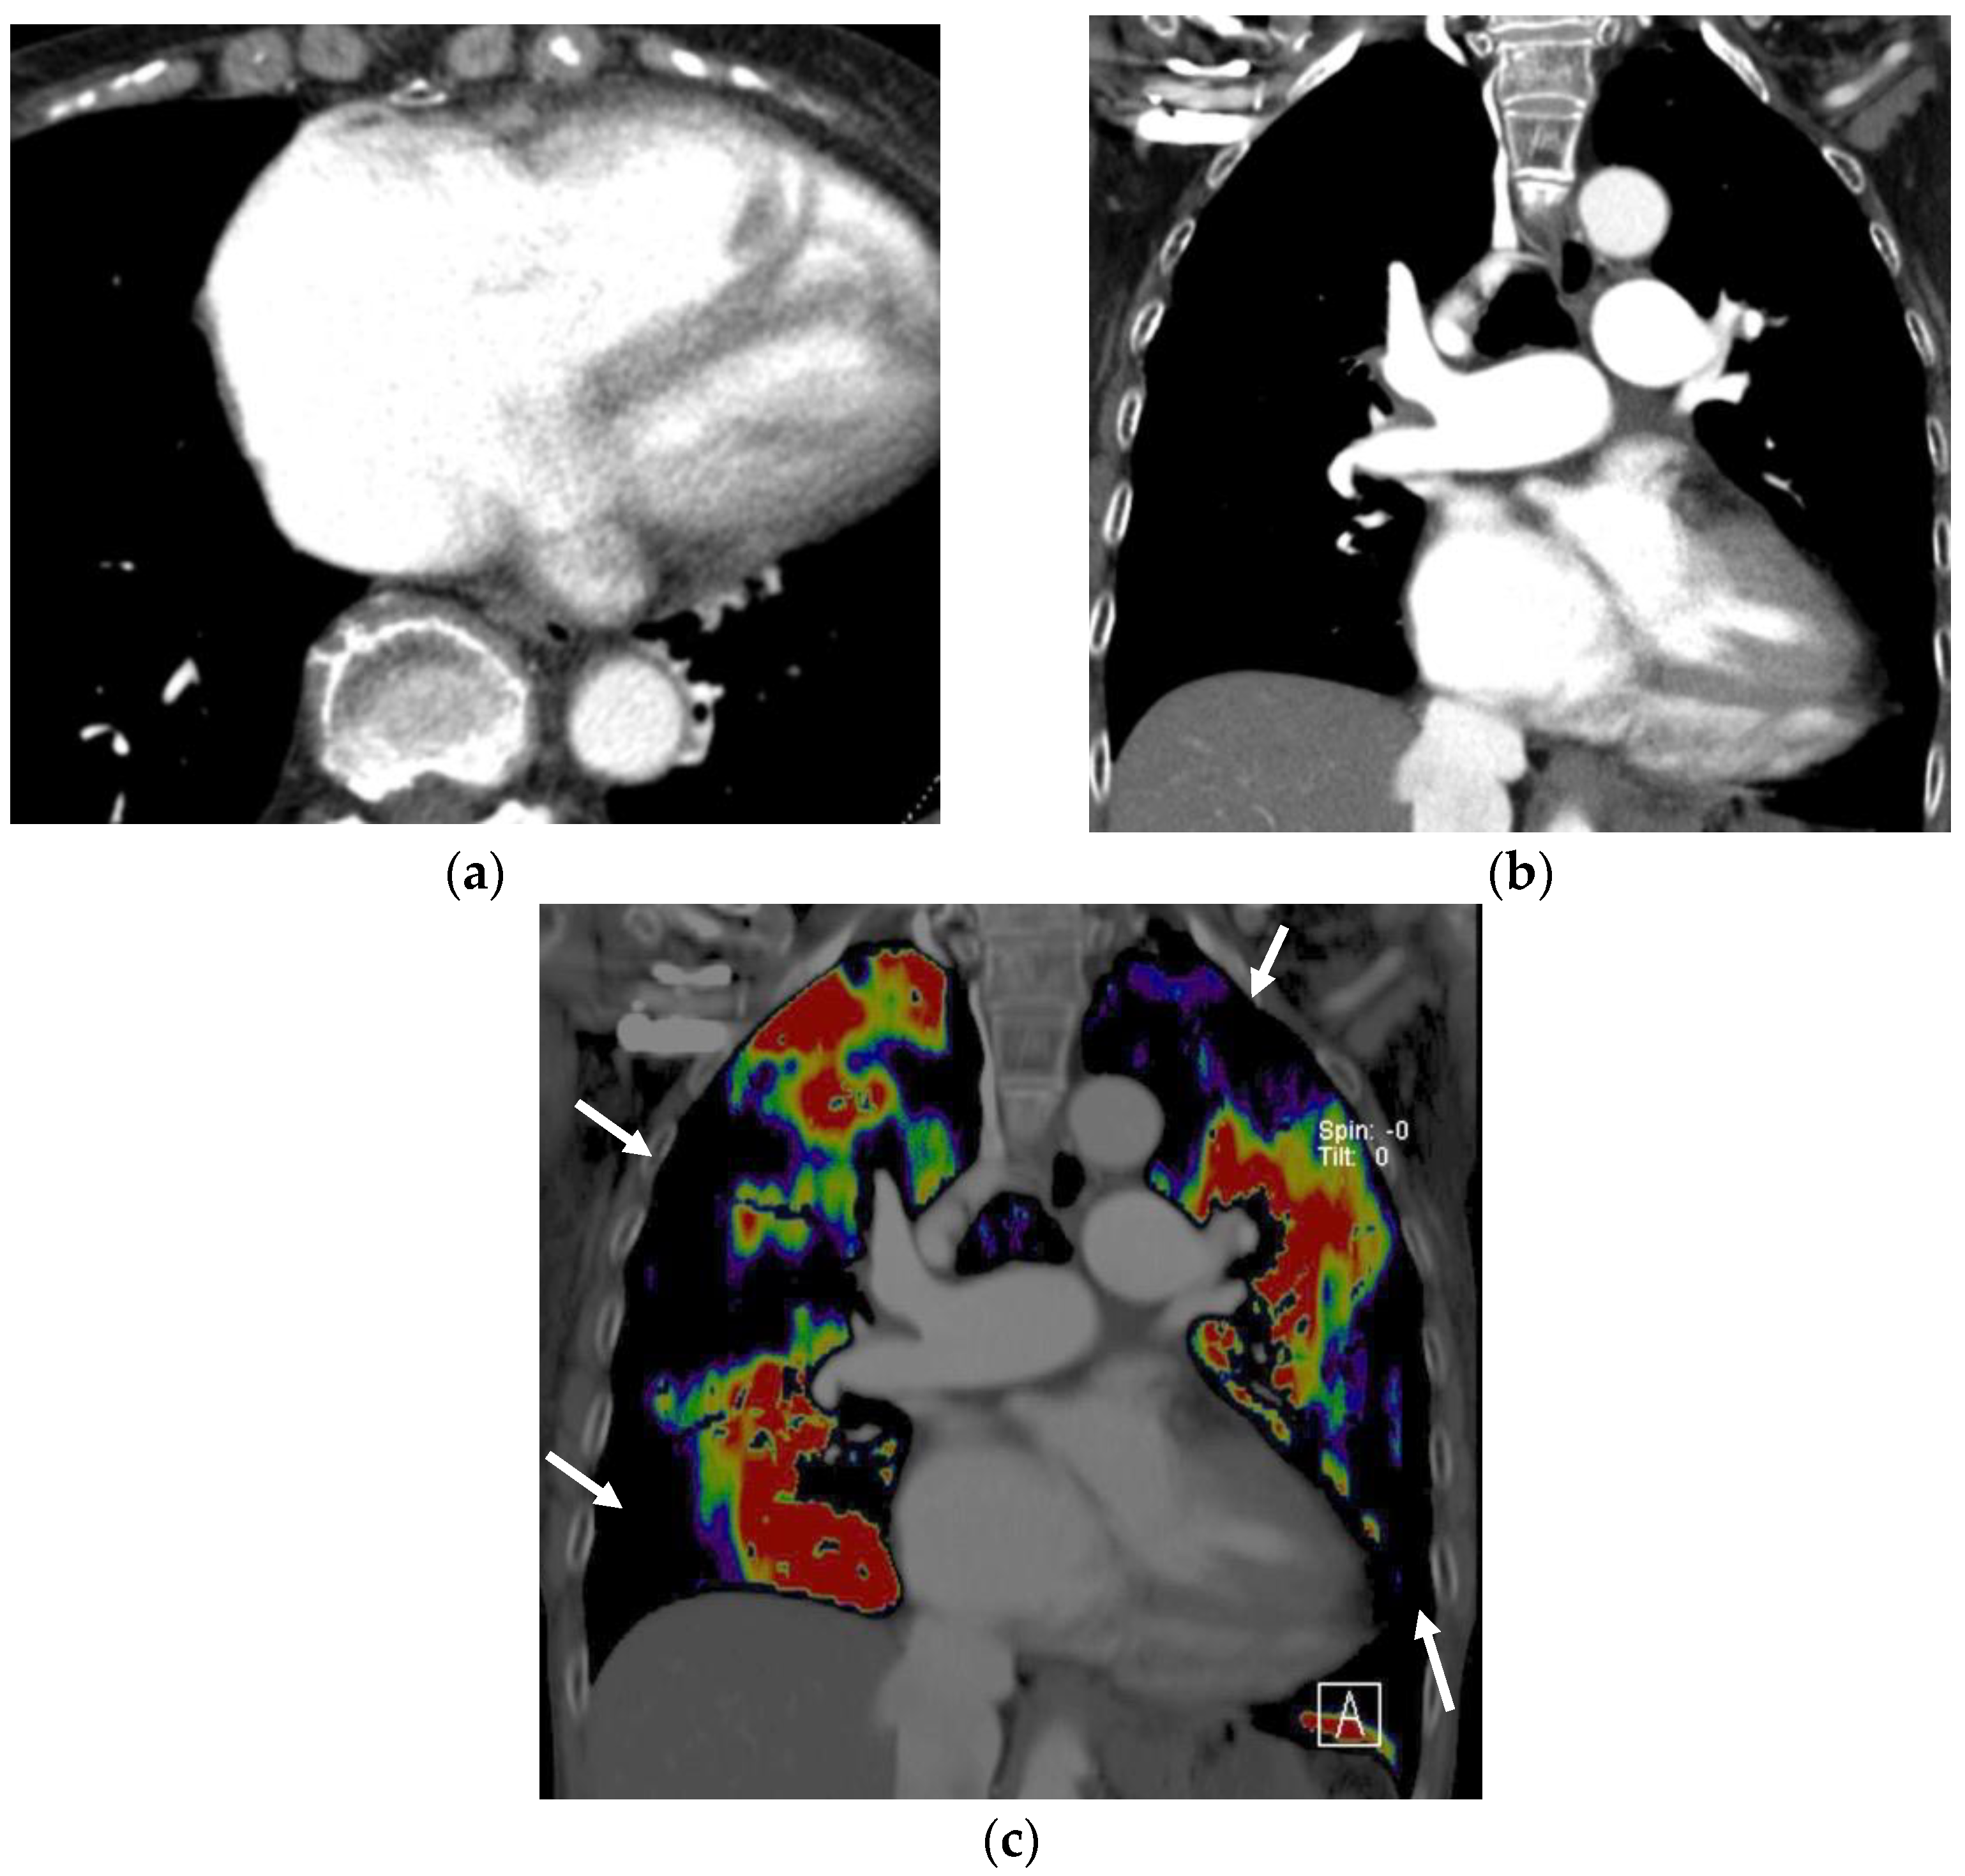

3.1.1. Perfused Blood Volume in the Lung

- Lu, G.M.; Zhao, Y.; Zhang, L.J.; Schoepf, U.J. Dual-energy CT of the lung. AJR Am. J. Roentgenol. 2012, 199, S40–S53. [Google Scholar] [CrossRef]

- Thieme, S.F.; Johnson, T.R.; Lee, C.; McWilliams, J.; Becker, C.R.; Reiser, M.F.; Nikolaou, K. Dual-energy CT for the assessment of contrast material distribution in the pulmonary parenchyma. AJR Am. J. Roentgenol. 2009, 193, 144–149. [Google Scholar] [CrossRef] [PubMed]

- Thieme, S.F.; Graute, V.; Nikolaou, K.; Maxien, D.; Reiser, M.F.; Hacker, M.; Johnson, T.R. Dual Energy CT lung perfusion imaging—Correlation with SPECT/CT. Eur. J. Radiol. 2012, 81, 360–365. [Google Scholar] [CrossRef] [PubMed]

- Masy, M.; Giordano, J.; Petyt, G.; Hossein-Foucher, C.; Duhamel, A.; Kyheng, M.; De Groote, P.; Fertin, M.; Lamblin, N.; Bervar, J.F.; et al. Dual-energy CT (DECT) lung perfusion in pulmonary hypertension: Concordance rate with V/Q scintigraphy in diagnosing chronic thromboembolic pulmonary hypertension (CTEPH). Eur. Radiol. 2018, 28, 5100–5110. [Google Scholar] [CrossRef] [PubMed]

- Miura, S.; Ohno, Y.; Kimura, H.; Kichikawa, K. Quantitative lung perfused blood volume imaging on dual-energy CT: Capability for quantitative assessment of disease severity in patients with acute pulmonary thromboembolism. Acta Radiol. 2015, 56, 284–293. [Google Scholar] [CrossRef]

- Hong, Y.J.; Kim, J.Y.; Choe, K.O.; Hur, J.; Lee, H.J.; Choi, B.W.; Kim, Y.J. Different perfusion pattern between acute and chronic pulmonary thromboembolism: Evaluation with two-phase dual-energy perfusion CT. AJR Am. J. Roentgenol. 2013, 200, 812–817. [Google Scholar] [CrossRef]

- Renard, B.; Remy-Jardin, M.; Santangelo, T.; Faivre, J.B.; Tacelli, N.; Remy, J.; Duhamel, A. Dual-energy CT angiography of chronic thromboembolic disease: Can it help recognize links between the severity of pulmonary arterial obstruction and perfusion defects? Eur. J. Radiol. 2011, 79, 467–472. [Google Scholar] [CrossRef]

- Bacon, J.L.; Madden, B.P.; Gissane, C.; Sayer, C.; Sheard, S.; Vlahos, I. Vascular and Parenchymal Enhancement Assessment by Dual-Phase Dual-Energy CT in the Diagnostic Investigation of Pulmonary Hypertension. Radiol. Cardiothorac. Imaging 2020, 2, e200009. [Google Scholar] [CrossRef]

- Sakamoto, A.; Sakamoto, I.; Nagayama, H.; Koike, H.; Sueyoshi, E.; Uetani, M. Quantification of lung perfusion blood volume with dual-energy CT: Assessment of the severity of acute pulmonary thromboembolism. AJR Am. J. Roentgenol. 2014, 203, 287–291. [Google Scholar] [CrossRef] [PubMed]

- Tsutsumi, Y.; Iwano, S.; Okumura, N.; Adachi, S.; Abe, S.; Kondo, T.; Kato, K.; Naganawa, S. Assessment of Severity in Chronic Thromboembolic Pulmonary Hypertension by Quantitative Parameters of Dual-Energy Computed Tomography. J. Comput. Assist. Tomogr. 2020, 44, 578–585. [Google Scholar] [CrossRef] [PubMed]

- Im, D.J.; Hur, J.; Han, K.H.; Lee, H.J.; Kim, Y.J.; Kwon, W.; Choi, B.W. Acute Pulmonary Embolism: Retrospective Cohort Study of the Predictive Value of Perfusion Defect Volume Measured with Dual-Energy CT. AJR Am. J. Roentgenol. 2017, 209, 1015–1022. [Google Scholar] [CrossRef] [Green Version]

- Ameli-Renani, S.; Ramsay, L.; Bacon, J.L.; Rahman, F.; Nair, A.; Smith, V.; Baskerville, K.; Devaraj, A.; Madden, B.; Vlahos, I. Dual-energy computed tomography in the assessment of vascular and parenchymal enhancement in suspected pulmonary hypertension. J. Thorac. Imaging 2014, 29, 98–106. [Google Scholar] [CrossRef]

- Abozeed, M.; Conic, S.; Bullen, J.; Rizk, A.; Saeedan, M.B.; Karim, W.; Heresi, G.A.; Renapurkar, R.D. Dual energy CT based scoring in chronic thromboembolic pulmonary hypertension and correlation with clinical and hemodynamic parameters: A retrospective cross-sectional study. Cardiovasc. Diagn. Ther. 2022, 12, 305–313. [Google Scholar] [CrossRef] [PubMed]

- Apfaltrer, P.; Bachmann, V.; Meyer, M.; Henzler, T.; Barraza, J.M.; Gruettner, J.; Walter, T.; Schoepf, U.J.; Schoenberg, S.O.; Fink, C. Prognostic value of perfusion defect volume at dual energy CTA in patients with pulmonary embolism: Correlation with CTA obstruction scores, CT parameters of right ventricular dysfunction and adverse clinical outcome. Eur. J. Radiol. 2012, 81, 3592–3597. [Google Scholar] [CrossRef] [PubMed]

- Takagi, H.; Ota, H.; Sugimura, K.; Otani, K.; Tominaga, J.; Aoki, T.; Tatebe, S.; Miura, M.; Yamamoto, S.; Sato, H.; et al. Dual-energy CT to estimate clinical severity of chronic thromboembolic pulmonary hypertension: Comparison with invasive right heart catheterization. Eur. J. Radiol. 2016, 85, 1574–1580. [Google Scholar] [CrossRef]